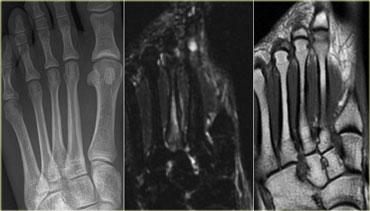

Bên trái là hình ảnh của bệnh nhân nữ 22 tuổi, vận động viên chuyên nghiệp với khởi phát đau vùng mu bàn chân gần đây, kéo dài sau khi tập luyện.

Tại thời điểm thăm khám, MRI cho thấy tăng tín hiệu trên chuỗi xung STIR và giảm tín hiệu trên chuỗi xung T1W (tức là gãy xương do stress độ 3).

Bên trái là hình ảnh của bệnh nhân nam 27 tuổi, cầu thủ bóng đá thi đấu ở giải nghiệp dư hạng cao nhất.

Bệnh nhân bị đau vùng giữa bàn chân với các triệu chứng gần đây có xu hướng tăng nặng.

Chuỗi xung T1W cho thấy đường gãy rõ ràng trong xương thuyền, gợi ý gãy xương do stress độ 4.

CT tương ứng cho thấy đường gãy và xơ cứng trên các ảnh cắt ngang và tái tạo mặt phẳng coronal.